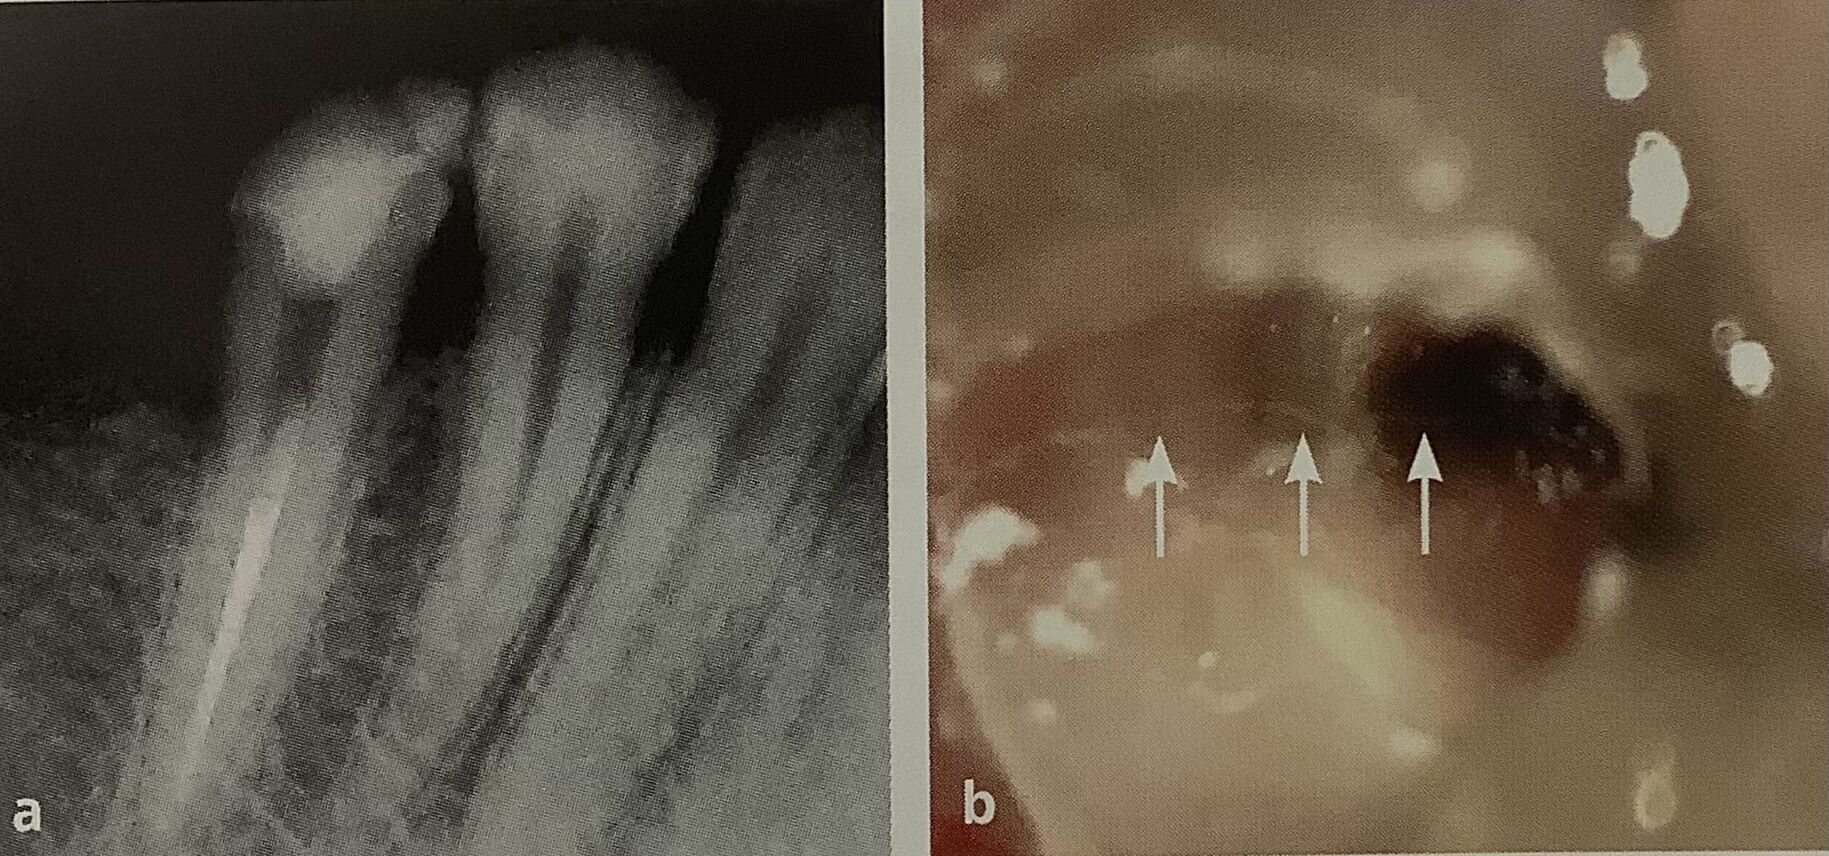

右が器具を入れて撮ったレントゲンで、

4本見えますか?

ピッタリ!

上手いですね!

矢印の所にヒビが見えます。